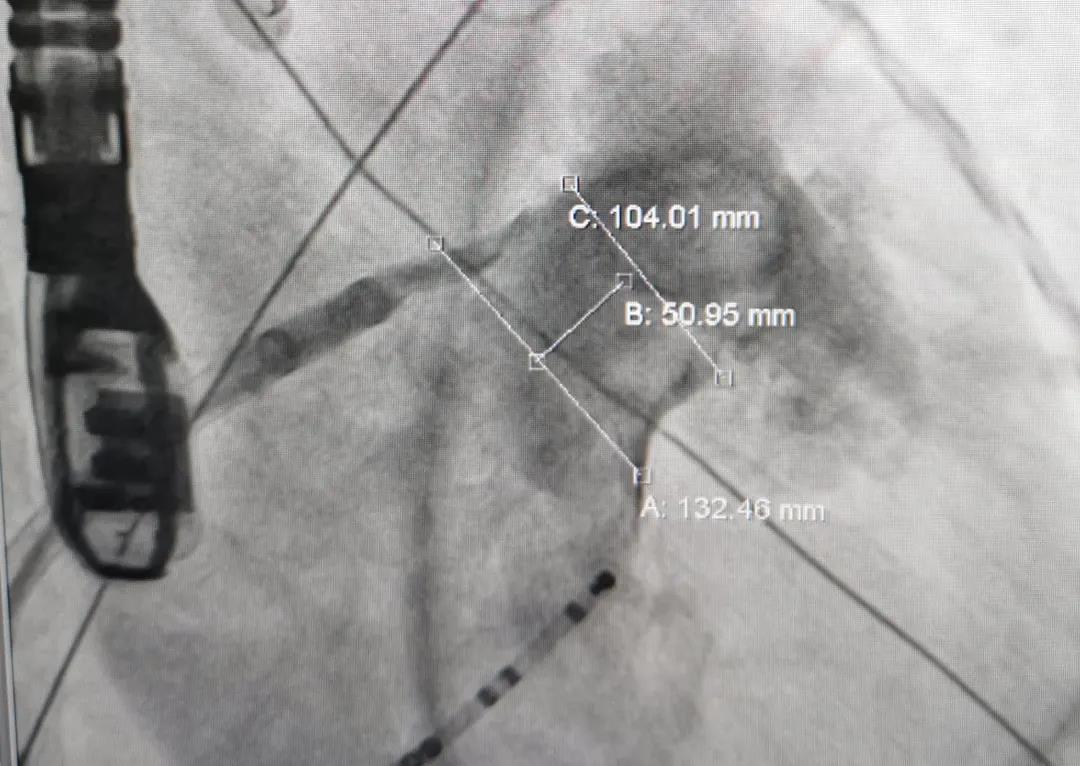

患者女性,71岁,因心慌气促20余天入院医治,患有高血压及糖尿病史。多角度丈量显示左心耳开口锚定区约为21mm,封堵区约为26mm,综合评估后选用LAmbre?2436封堵器,造影及食路超声显示无残存分流,患者术钟注术后无不适,手术圆满成功。